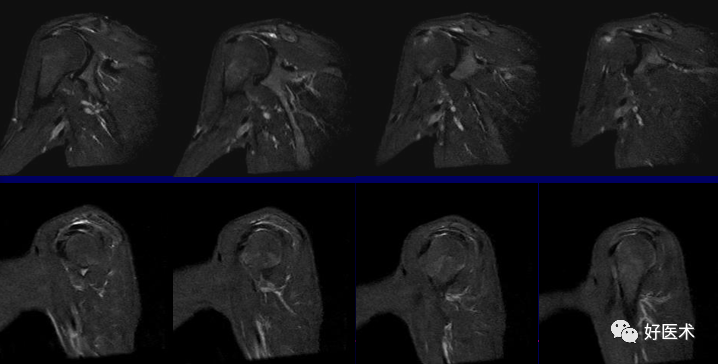

斜冠状位:取横断位作定位像,扫描层面与冈上肌腱平行,扫描范围为锁骨外端至肩峰。

斜冠状、斜矢状:显示肩袖及冈上肌走行、显示喙肩弓。

轴位:显示肩胛下肌腱撕裂、盂唇撕裂

冠状位:显示肩袖撕裂、盂唇撕裂

矢状位:显示肩袖撕裂、盂唇撕裂

(2)肩袖撕裂

冈上肌腱最易发生。

正常、异常肩袖肌腱和邻近软组织结构的MR表现

冈上肌腱不完全撕裂

冈上肌腱不完全撕裂伴肩峰下囊积液

冈上肌肌腱损伤(撞击),肩胛下滑囊积液(肩胛下肌腱损伤?)

冈上、下肌腱撕裂、肩胛下囊积液